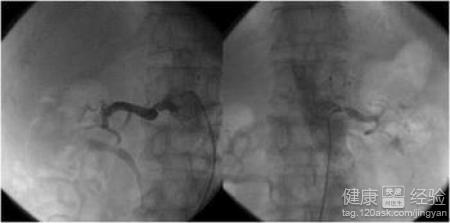

冠心病是冠狀動脈粥樣硬化的簡稱,它是發生心絞痛、心肌梗死的基礎,所以我們要做好冠心病的預防,那麼如何預防冠心病呢?